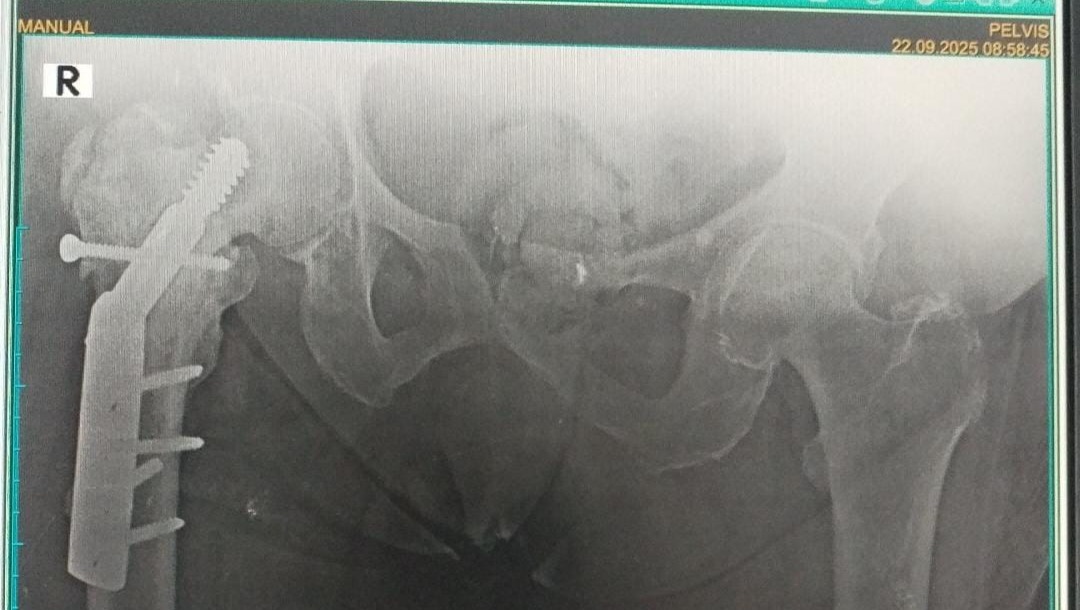

En la radiografía anexa a este mensaje, se ve que el sistema metálico que le habían puesto antes (un tornillo especial llamado DHS) nunca funcionó bien y la cadera ahora tiene una deformidad causada por la fractura previa.

Por eso, tres médicos especialistas, distintos al primero, recomiendan una segunda cirugía para retirar ese material que ya no sirve y reemplazar toda la cadera derecha con una prótesis híbrida (una cadera artificial). Esta prótesis combina diferentes materiales: una parte que se fija en el hueso con o sin cemento, y una articulación hecha de metal y plástico resistente para que pueda volver a moverse mejor y sin dolor. (Para detalles, ver el informe anexo).

Sadly, on 21 September, everything changed. She suddenly felt a loud click in her hip, followed by unbearable pain. X-rays show that the metal implant from her first operation has failed, leaving her unable to walk and in constant pain.

Three specialists now recommend a total hip replacement with a hybrid prosthesis. But in Venezuela’s ongoing economic and healthcare crisis, the cost of surgery must be paid privately and in advance.